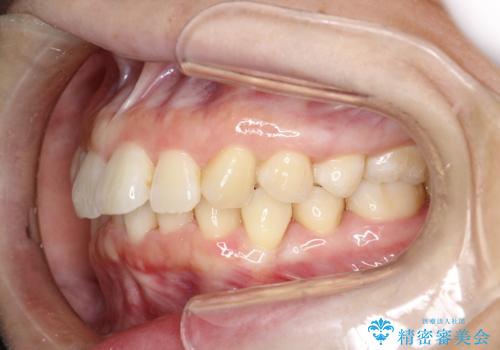

インビザライン ライトパッケージによる部分矯正治療 下の前歯のみの歯並び改善

- インビザライン ライトパッケージパーシャル(下顎のみ)

- 下の前歯の歯並びのみの改善をご希望されました。

インビザライン ライトパッケージ下顎のみ(1枚~14枚まで)での治療を行なっていきました。

マウスピース枚数 初回14枚 + 追加13枚

概ね7ヶ月で治療完了しました。

インビザラインのライトパッケージでは14枚までという枚数制限がありますが、限られた枚数の中で当院独自の工夫を随所に盛り込み、狙い通りの治療結果が得られました。